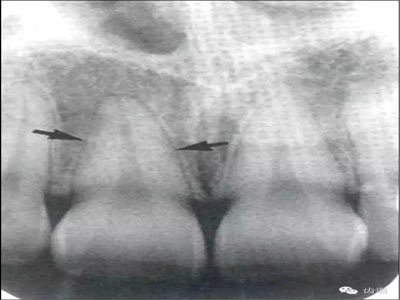

牙頸部Burnout征象:有時因投照技術(shù)問題而造成牙頸部近中或遠(yuǎn)中呈低密度影像,位于牙釉質(zhì)和牙槽嵴頂之間。